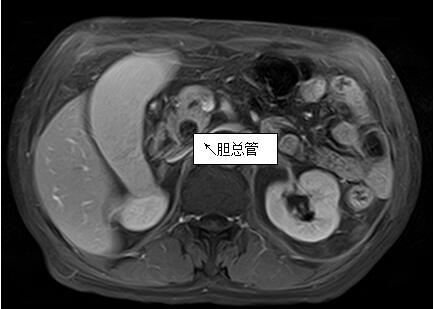

69歲王姓患者,因“發(fā)現(xiàn)無痛性黃疸1月”入院,根據(jù)患者病史,患者診斷傾向于壺腹部腫瘤所致梗阻性黃疸。予以完善腹部CT及上腹部MRI加MRCP均顯示肝內外膽管擴張,未發(fā)現(xiàn)明顯膽管,胰腺及十二指腸乳頭部腫瘤,且患者CA199正常。以前醫(yī)院未引進超聲內鏡,這類患者到此就遇到診斷瓶頸。此患者經過消化內科張丹霞副主任醫(yī)師完善超聲內鏡檢查后,可以清楚顯示膽總管下段壁內軟組織占位?;颊咄ㄟ^超聲內鏡檢查診斷明確,轉至肝膽外科行手術治療。

上腹部MRI圖片